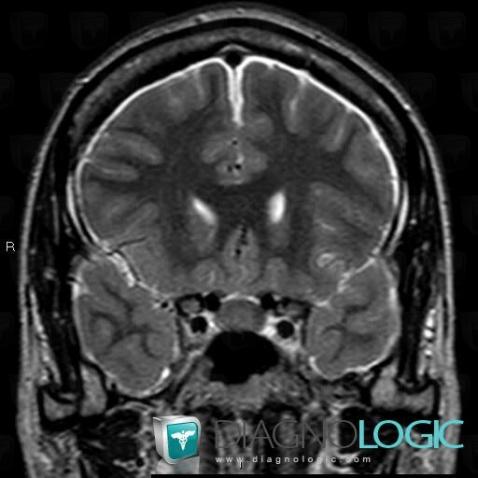

Voici les informations spécifiques à l'image clé ci dessus:

- Diagnostic Hypotension intracrânienne , Localisation(s) Espaces peri cérébraux supratentoriels, comportant les gammes Réhaussement méningé diffus